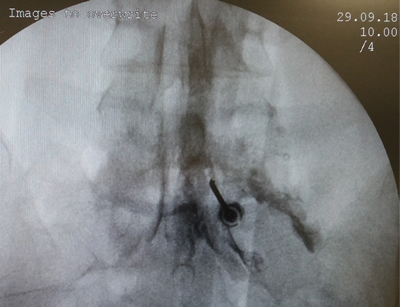

Los procedimientos fueron realizados en sala de operaciones, con anestesia local con lidocaína al 0,5 %, mediante abordaje interlaminar parasagital homolateral al dolor en los espacios L4-L5 o L5-S1, con aguja de Tuohy número 17 o 18, 3½ o 4¾ pulgadas según la complexión física del paciente, con identificación del espacio epidural mediante pérdida de resistencia con suero fisiológico. Se utilizó iopamiron como medio de contraste para visualizar el epidurograma (Figuras 1 y 2).

Fig. 1. Enfoque radiológico anteroposterior de la inyección de contraste en el espacio epidural, durante una inyección epidural de esteroides mediante el abordaje interlaminar parasagital derecho a nivel del espacio L5-S1.